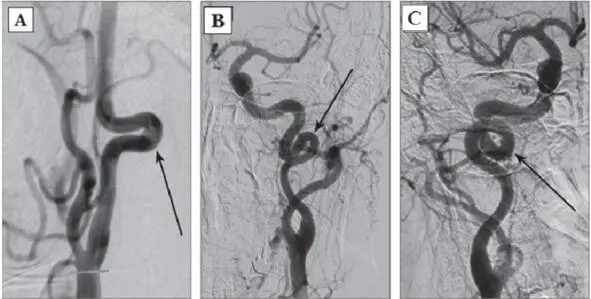

Type 3: artery kink at an angle less than 30°(Fig. 2C) [182].

Presently, the modified J. Weibel – W. Fields and H. Metz classification is actively used:

1. Tortuosities: C- and S-shaped elongation of the ICA or deformation along the ICA course (Fig. 3A, B);

2. Insignificant deformation: angulation or kink between two ICA segments with a loop formed at an angle exceeding or equal to 60°, causing a local stenosis of a major artery (Fig. 2A);

3. Moderate deformation: angulation or kink between two ICA segments with a loop formed at an acute angle equal to 30—60°, causing a local stenosis of a major artery (Fig. 2B);

4. Marked deformation: angulation or kink between two ICA segments with a loop formed at an acute angle less than 30°, causing a local stenosis of a major artery (Fig. 2C);

5. Looping or knotting: excessively long ICA forming a marked S-shaped tortuosity or an annular configuration, where more than two ICA segments lying on different planes are involved in the process (Fig. 3C) [264].

Fig. 3: Types of pathological deformations based on CAG: A – C-shaped tortuosity of ICA (arrow indicated); B – S-shaped tortuosity of ICA (arrow indicated); C – ICA loop (arrow indicated).